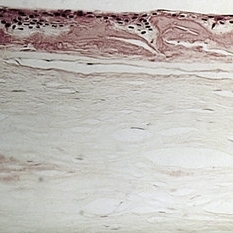

Slide 7-109

Feb 25 2019 by Lancaster Course in Ophthalmology

Lamellar graft. Descemet's membrane and endothelium are not present.

Condition/keywords: lamellar graft